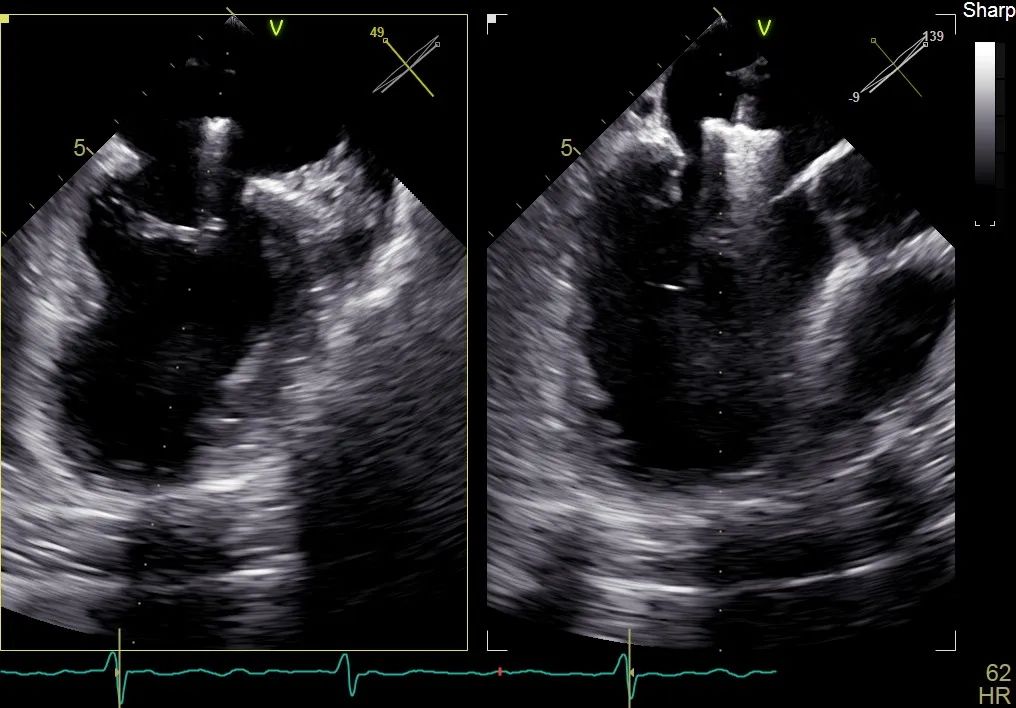

术前行经食道超声评估:继发性二尖瓣反流,反流程度4+;二尖瓣有效反流口面积(EROA) 0.81 cm²,缩流颈宽度18 mm,反流容积112.36ml,二尖瓣瓣口面积5.06 cm²,平均跨瓣压差5 mmHg,二尖瓣前叶(A2)长度15mm,二尖瓣后叶(P2)长度9 mm;左房内径54mm,左室收缩末期内径50mm,左室射血分数43%,肺动脉压83 mmHg。

术前食道超声可见二尖瓣重度反流,前后叶对合不全伴有间隙,且反流束宽度18mm